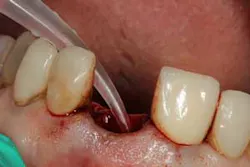

Although the literature varies as to the amount of bone volume that can be created/preserved, what material to use, as well as the indications for these procedures, (4) the majority of these studies agree that socket debridement is essential post-tooth extraction to ensure a good result. Socket debridement is particularly important when acute/chronic infections are present and cystic material lines the alveolar socket and/or tooth (figures 1 and 2). The complete removal of this infected tissue (figure 3) is tantamount to good bone fill, and can be the source of bone-graft contamination and infection.

After removal of the tooth, there are many methods of debriding the socket and various instrumentation that one can use. This author chooses to use a spoon excavator or spoon curette with serrations as a means of performing mechanical debridement (figure 4). After mechanical debridement, copious saline is used to irrigate the socket (figure 5), followed by the placement of cotton pellets soaked with either tetracycline (50 mg/ml) or 60% citric acid into the socket. After chemical modification, the socket is again irrigated and flushed with saline.